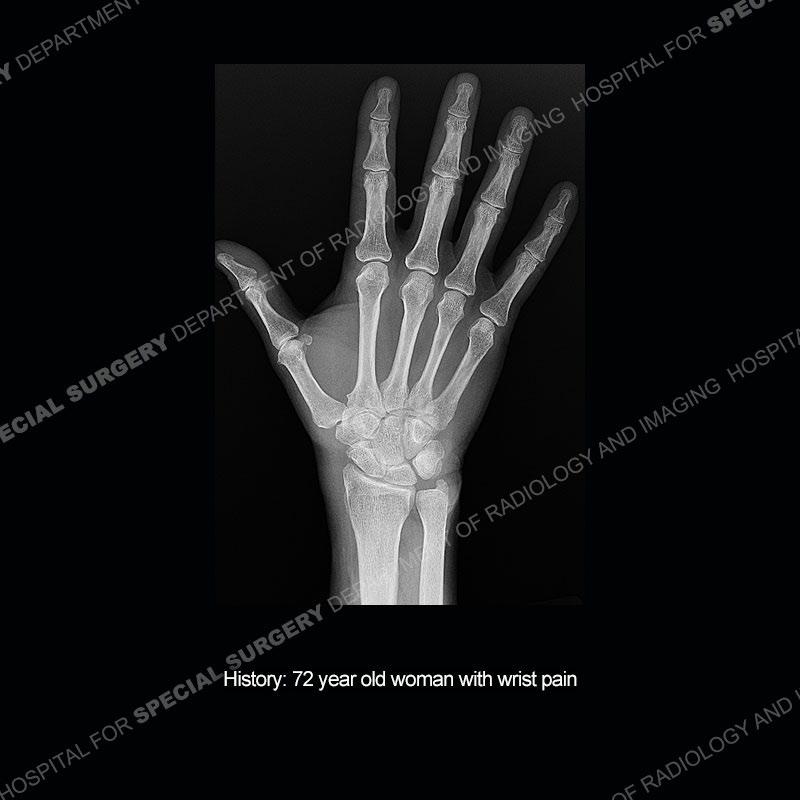

The radiographs in this case are not particularly contributory. The MRI demonstrates tenosynovitis of the first extensor compartment manifest by fluid/synovitis distention of the tendon sheaths. Multiple tendon slips are present of the abductor pollicis longus (APL) and with severe tendinosis seen of one of the tendon slips. Other areas of slightly increased signal and tendinosis are present of the components of the APL. Noted is a somewhat prominent septum separating the more dorsal extensor pollicis brevis (EPB) from the APL.